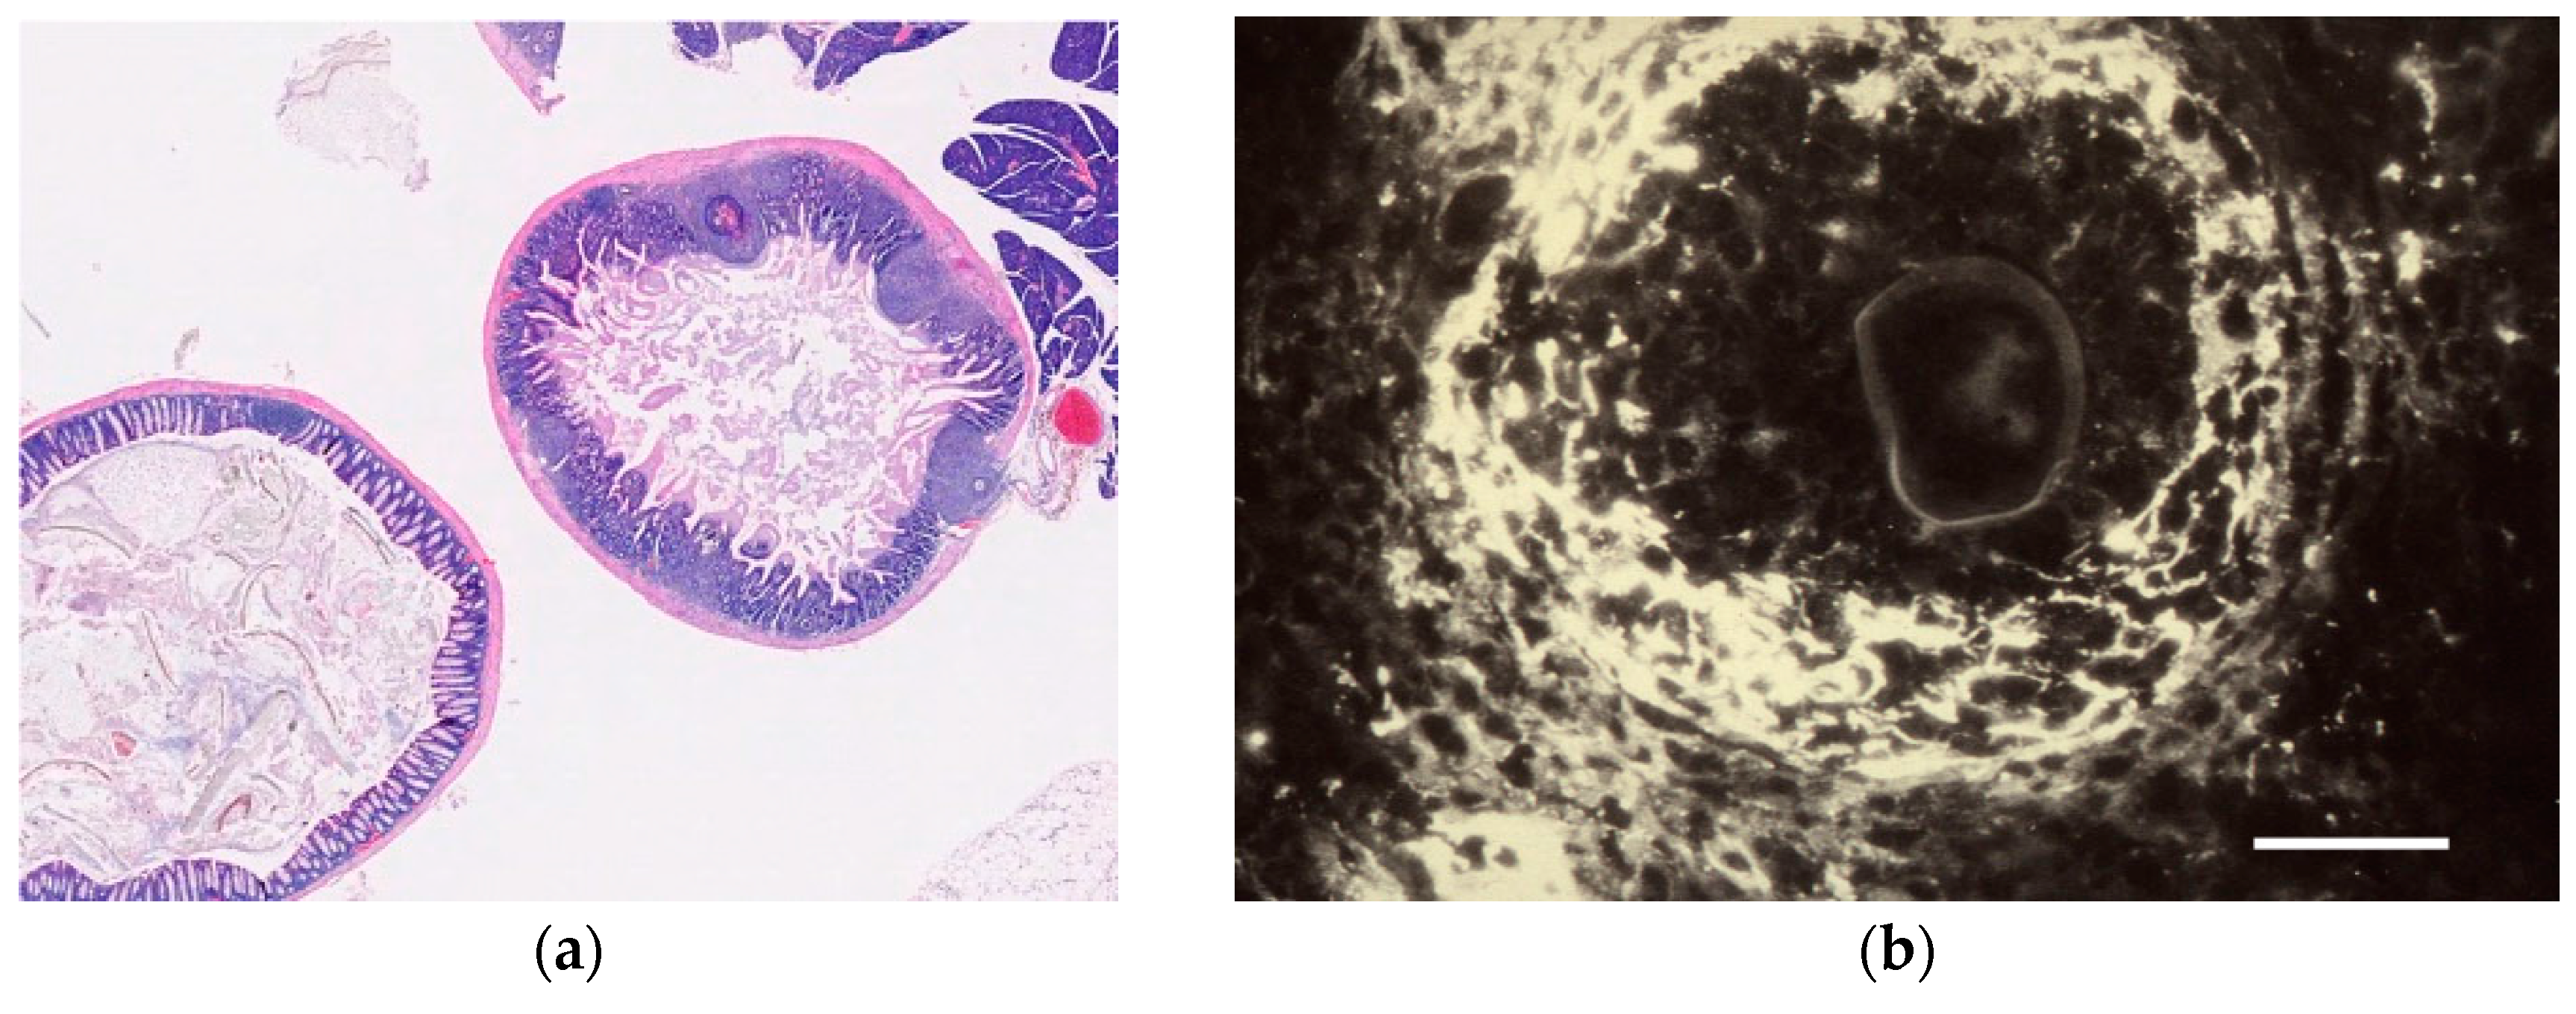

3.1.1. Eggs and Miracidia

3.1.2. Cercaria

3.1.3. Adult Worms

- Farah Ahmed, S. Urinary tract complications of chronic Schistosoma haematobium infection and immunohistology of granuloma formation. Master’s Thesis, Karolinska Institutet and Somali National University, Mogadishu, Somalia, 1986. [Google Scholar]

- Linder, E. Cercarial kissing marks-no superficial make-up. Parasitol. Today 1990, 6, 393–395. [Google Scholar] [CrossRef]

- Linder, E. Identification of schistosomal eggs: Description of an immunological spot assay for hatch fluid antigen. J. Immunol. Methods 1986, 88, 137–140. [Google Scholar] [CrossRef]